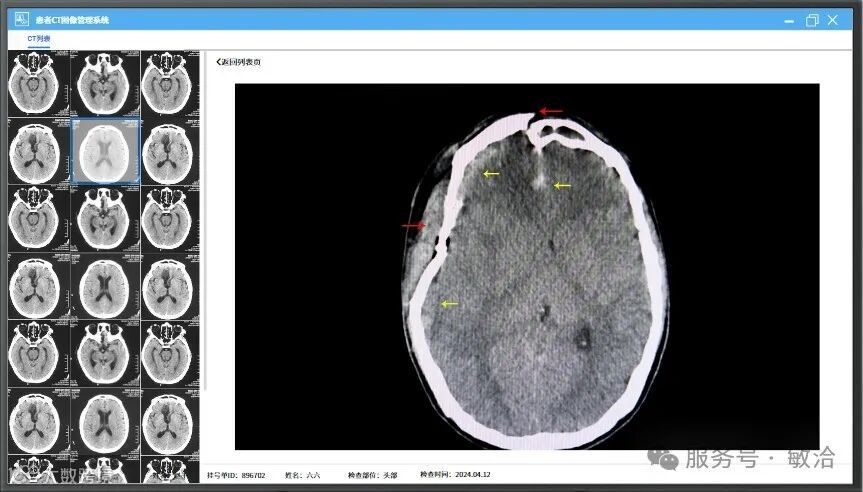

超声聚焦设备上位机系统,主要分为患者管理系统、CT管理系统、治疗计划系统和设备控制系统。通过前三个系统操作,生成治疗计划。医生输入挂号单ID后,软件获取到治疗计划信息,以表格形式展现在软件界面上,软件默认按获取到的靶点顺序依次进行治疗。医生可以点击选择任一个靶点立即进行治疗。该软件为医生提供了工具来制定和优化患者的放疗计划,提高治疗效果。